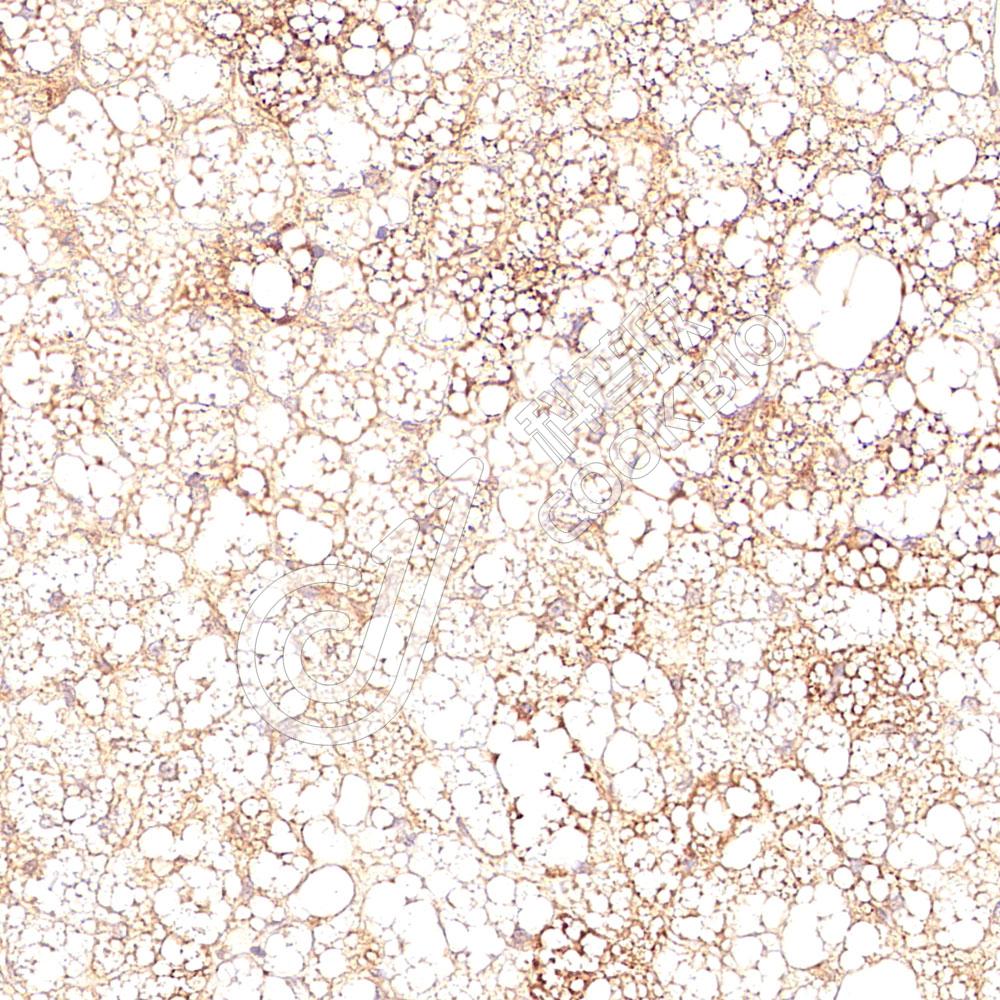

IHC检测Adiponectin蛋白(货号 K1346743).

样品: 小鼠棕色脂肪, 4%多聚甲醛 (货号KSG1101) 固定12-24小时.

抗原修复: Tris-EDTA抗原修复液(pH 9.0) (KSG1203), 98℃, 20分钟.

—抗: 1: 200稀释, 4℃ 孵育过夜.

二抗: S-vision免疫组化多聚二抗(山羊抗兔),即用型 (货号KB3906), 室温孵育20分钟.

样品: 大鼠棕色脂肪, 4%多聚甲醛 (货号KSG1101) 固定12-24小时.